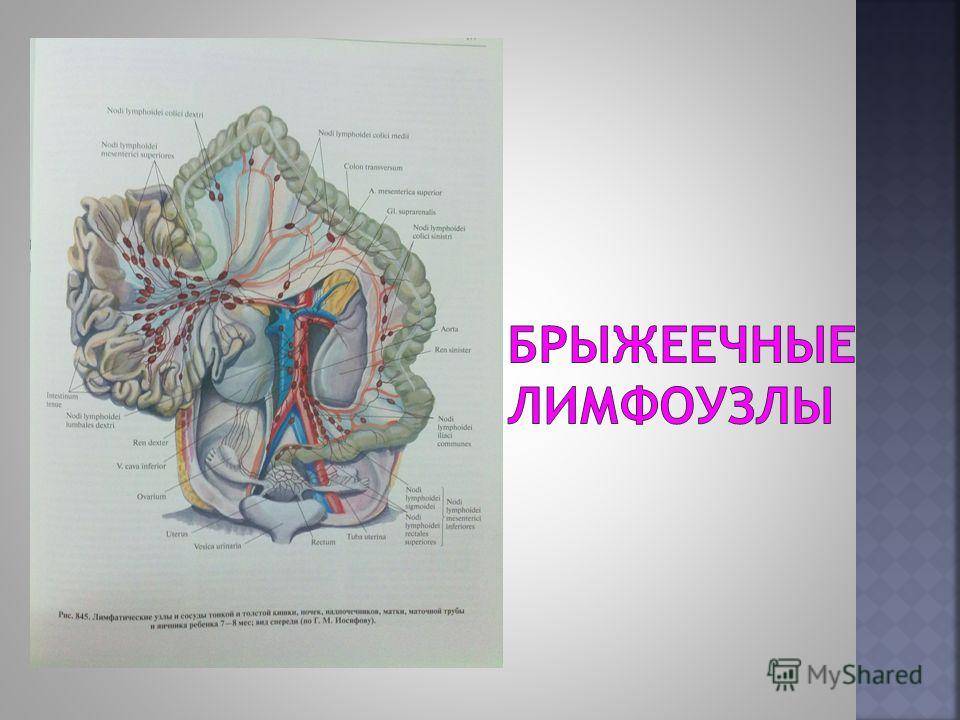

Мезентериальные лимфатические узлы: УЗИ и диагностика